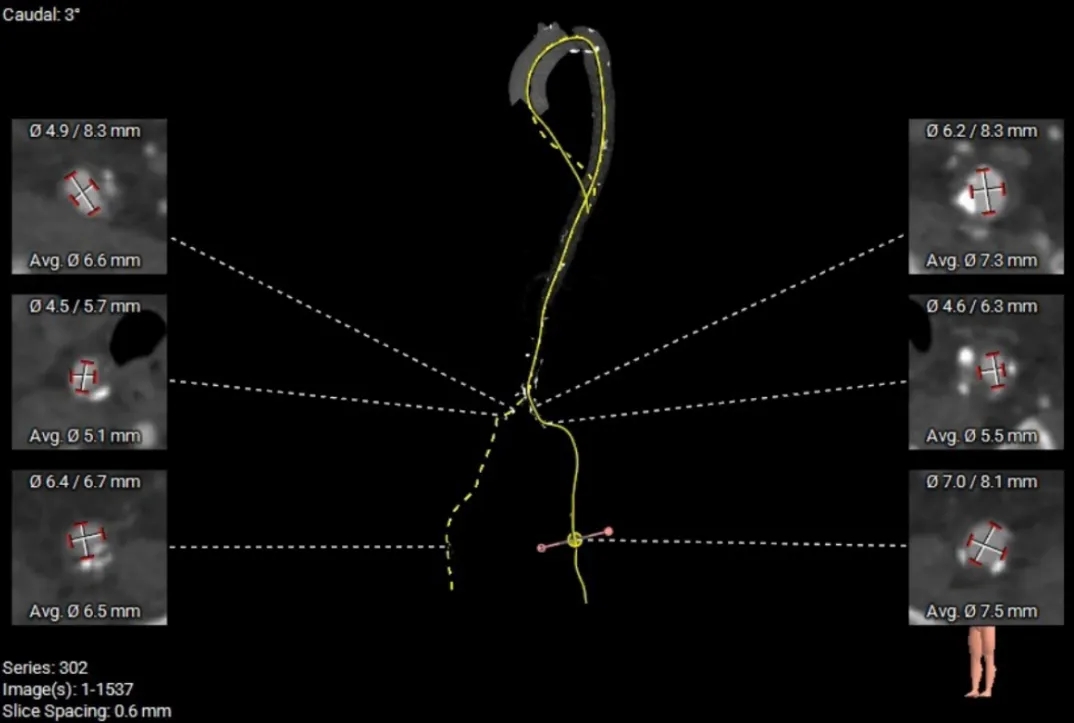

术前CT分析

主动脉根部测量

Annulus 20.7mm

LVOT 21.3mm

钙化积分 612

SOV

27.9*26.8*27.1mm

STJ 22.6mm

AAO 28.8mm

-

三叶瓣

流出道直筒型

重度钙化

STJ及升主无明显扩张

瓣上结构测量

瓣上2mm

20.5mm

瓣上4mm

19.9mm

瓣上6mm

20.7mm

瓣上8mm

20.2mm

瓣上10mm

20.8mm

瓣上12mm

21.9mm

冠脉风险评估

LCA Height

RCA Height

左冠开口高度较低,结合瓦氏窦大小,预估冠脉风险相对较低。

左室测量

左室内径可,心室壁增厚,心尖较薄,注意导丝位置及形态,避免左室损伤。